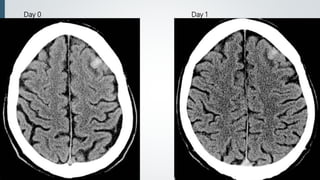

CT findings

 Early

 Patchy, ill-defined, low-density edema with small foci of

hyperdense hemorrhage

 24-48 hours

 Edema, hemorrhage and mass effect often increase

 New foci of edema and hemorrhage may occur.

 Chronic

 Become isodense (at 2 weeks ) then hypodense

 Encephalomalacia with volume loss (at 1 month)

 Repeat CT recommended if initial exam negative but symptoms persist for

24-48 hours.

Day 0 Day 1

Day 10